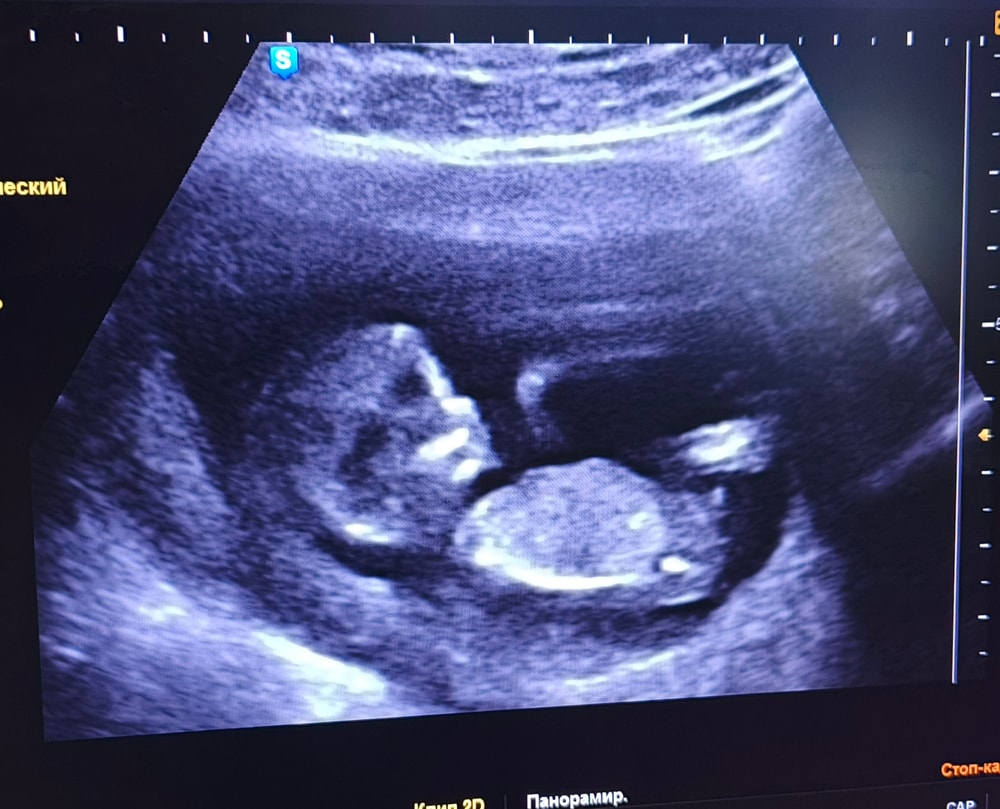

Пол малышаВсем привет, девочки. Кто уже на опыте ,помогите понять мальчик/девочка?))Здесь 12 недель

Похоже на мальчика)

У Вас по очертаниям на мальчика похож)